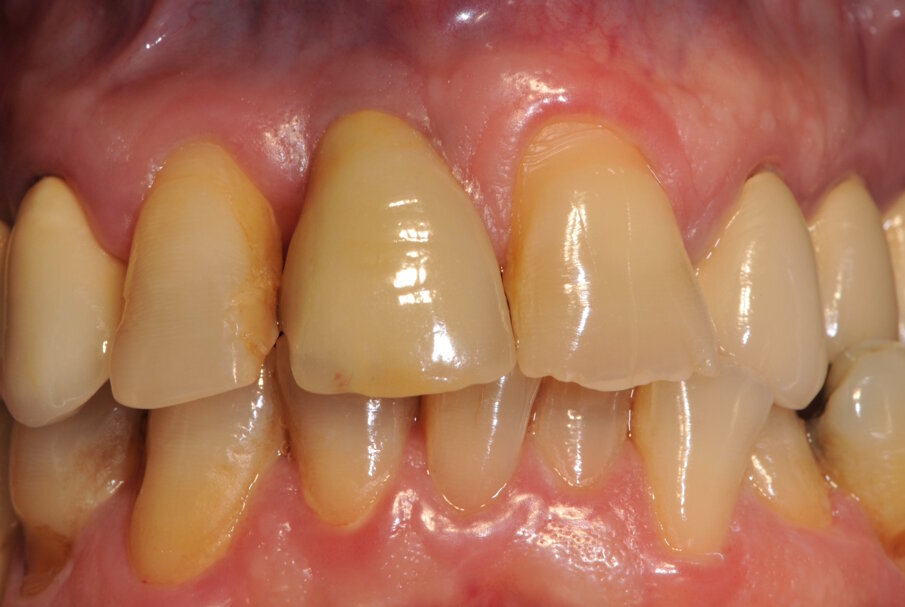

Fig. 10_Corona definitiva appena cementata con tecnica extraorale.

Paziente di sesso maschile di 60 anni di età giunto alla nostra osservazione per una edentulia parziale dovuta all’assenza dell’elemento 1,1. La situazione clinica è resa esteticamente e funzionalmente complicata dalla assenza dell’elemento 2,2 che considerato lo spostamento dei denti contigui comporta un aumentato spazio per la sostituzione protesica dell’elemento 1.1. Si effettua dopo rx di controllo il posizionamento di un impianto osteintegrato GTB diametro 3,6 x 9 mm ,con posizionamento, come da protocollo, 1,5 mm sottocrestale ed inserzione immediata di moncone easy abutment slim 3,4 x 7 mm altezza gengivale 3,5 mm. angolato a 10 gradi (Easy Abutment Slim – GTB Plan1Health Amaro, UD, Italy). Con l’ausilio di una cappetta easy si costruisce e si cementa, con tecnica extraorale, una corona provvisoria in resina acrilica con forma a pontic su elemento 1.1 in modo da eseguire un carico immediato e fornire al paziente una estetica immediata (Figg. 1-3). Dopo 12 settimane ad avvenuta osteointegrazione si provvede all’impronta definitiva eseguita a livello abutment con elastomero di precisione Aquasyl Monophase (Dentsply) e con idonea cappetta easy (GTB Plan1Health Amaro, UD, Italy). La stessa cappetta easy viene utilizzata dal laboratorio odontotecnico come cappetta da sovrafusione garantendo standard di precisione stabiliti industrialmente (Figg. 4-8). La corona costruita in lega preziosa e porcellana viene cementata dopo una settimana, fatte le prove estetiche e occlusali necessarie sul paziente. I controlli a distanza di 4 anni, sia radiografici che clinici, confermano la stabilità dell’osso intorno all’impianto e la mancanza di perdita di tessuto gengivale attorno allo stesso (Figg. 9-11).